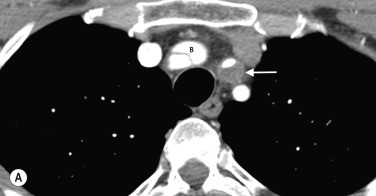

Anatomical mapping of thoracic or abdominal coarctation are well performed by both CT and MR, although by using phase-contrast techniques both the extent of collateral flow and peak velocities (V) through the area of maximum stenosis can be measured with MRI. The pressure gradient can then be estimated using a modified Bernoulli equation (Δ P = 4V 2 ) which can be useful for assessing change at follow-up ( Figs 77.4 and 77.5 ).

Fig. 77.4, Thoracic Aortic Coarctation in a Young Patient With Severe Upper Limb Hypertension.